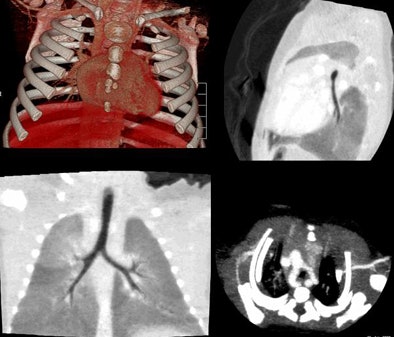

| Nearly whole-body imaging in a single rotation reveals lung changes and pleural thickening. |

| Feeding artery is visible at 320-detector-row CT in a patient with pulmonary blastoma. |